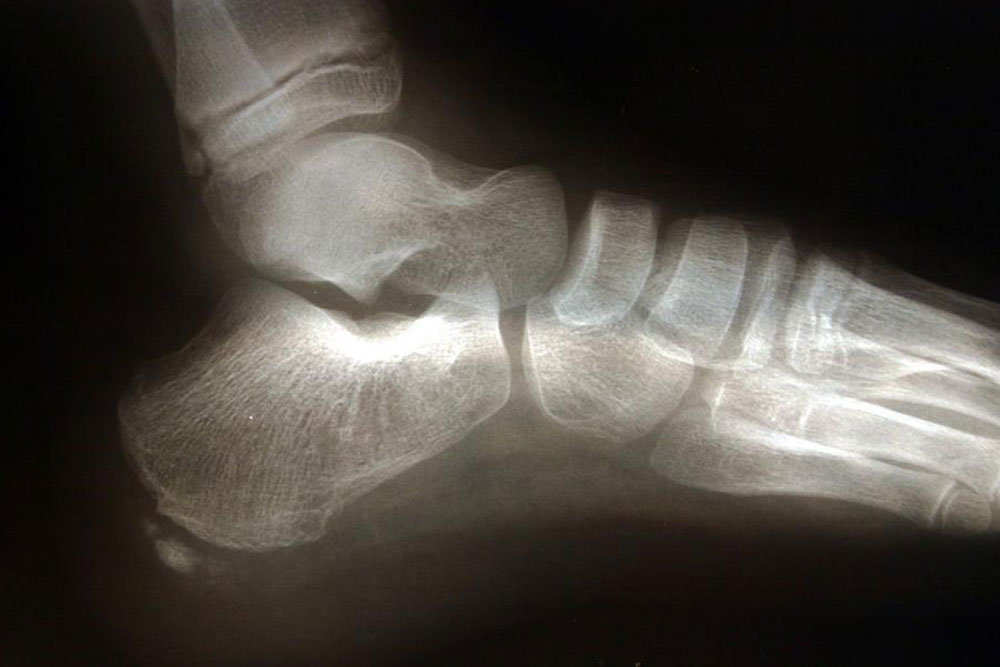

Commonly affecting athletes who frequent activities include running and jumping, heel spur is caused due to calcium deposits on the underside of the heel bone. The symptoms include inflammation of tissues and tendons near the spur, pain while walking or jogging, formation of calluses, swelling or redness of the affected part of the heel. The pain that is experienced is often sharp and stabbing. Sometimes that pain can go away to be replaced by a dull throbbing that aggravates while doing activities such as walking, jumping, jogging, or running.